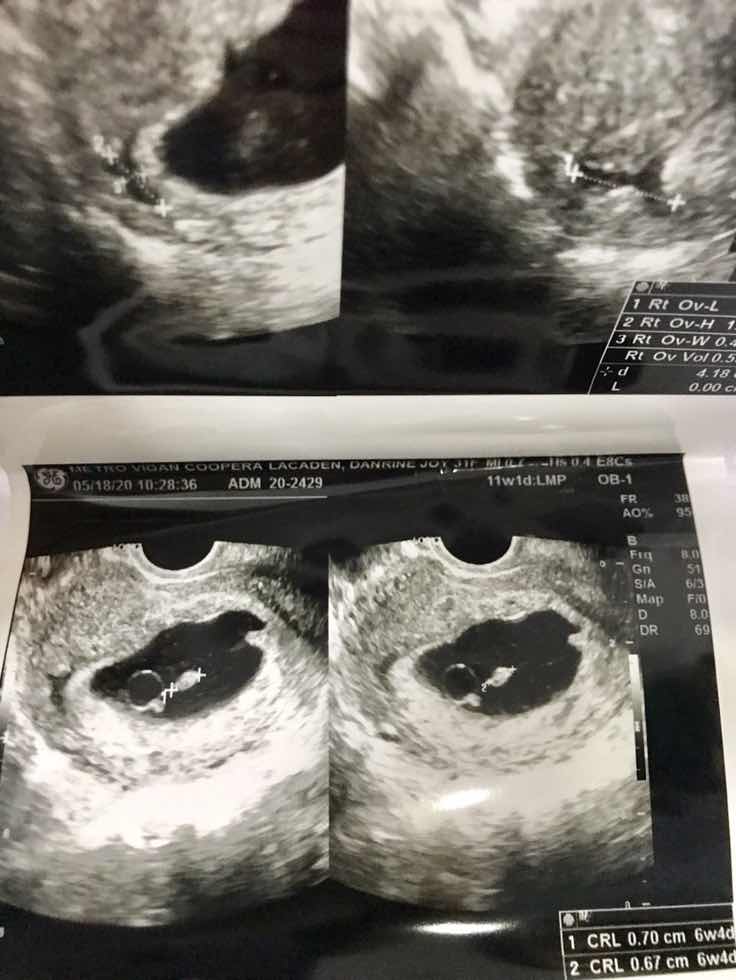

Hello po sa lahat ng mga katulad ko ng pinagdaanan at pinagdadaanan I just got home from my dilatation and curettage yesterday and today is the first day that I am not carrying my baby anymore. Pain is not easy and fear is a true enemy but then I want to say that God remains faithful. Mahirap po ang mawalan ng isang blessing dahil alam natin na ipinagdasal ito ngunit mas mahirap na mawalan ng pagtitiwala natin sa ating mga sarili, sa mga minamahal natin at higit sa lahat sa ating Dios. Gusto ko lang ishare sa inyo na it’s okay to mourn and cry but we have to deal with the reality of surrendering all to God and moving forward with Him. It’s not yet the end of His great plan for us. I lost my baby on my 11th week, he/she only developed for 6 weeks and 4 days aog. I’m 31 years old and got married last year. Nakakatakot po yong mag undergo sa process ng pagraspa dahil sa experience ko they had to induce ng over 10 hrs then I also had infection tapos first pregnancy ko pa ito. Then here comes the process of grieving and acceptance. Narealize ko na mas nakakatakot yong mawawalan tayo ng pag-asa. Hindi magiging madali but we always have a lot to be thankful for like this life filled with the love of the Lord, for a loving husband and family, supportive friends and for better things ahead. Para sa lahat po ng katulad ko, magpakatatag tayo. Pinili tayo Ni God for a purpose and sana maging insipirasyon ito sa lahat. If you’re expecting, pregnant, mothering or still trying to have one, be encouraged. He makes everything beautiful in His time. Thank you for reading! Sa Diyos ang papuri. Life is a precious gift. ?